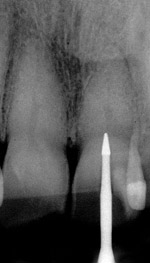

Figure 1 shows a radiograph of a typical maxillary first molar. Upon extraction, the apical anatomy was immediately studied and photographed under a global microscope (Figure 2, Figure 3, Figure 4, Figure 5 and Figure 6). That is a take-home lesson; the extracted teeth should be studied with loupes or microscopes. These photographs demonstrate an important lesson. The two-dimensional radiograph shows three roots. In reality, however, a significant percentage of maxillary first and third molars—80% in some studies—have four roots and four or more canals. 1,2 While the MB and MP (MB-2) roots are usually fused, their morphology is unique. For diagnostic, access, and shaping purposes, it is safer to think of them as separate roots. Wisdom teeth often exaggerate the anatomic features of first and second molars, and a significant percentage of maxillary third molars have four distinct roots. The author's personal bias is to consider most maxillary first the radiographic apex of the tooth. The use of the radiographic root apex for use as the reference point for measuring the apical extent of the root filling is the common standard, yet has been criticized because of the poor correlation between the location of this point and the actual canal foramen. 5 The illustrations used in advertising and manufacturer's "tip cards" only further the notion of simple foramen anatomy. While simple anatomy is often the case with incisor teeth, a quick perusal of the posterior teeth in Brown and Herbransen's Dental Anatomy & 3D Interactive Tooth Atlas demonstrates that a significant portion of the foramen exit short of the apex and have multiple foramina. 6 The same extracted tooth in Figure 2 demonstrates that the palatal foramen is more than a millimeter short of the radiographic apex. If this tooth were filled to the constriction, which for arguments sake is 0.75 mm from the foramen, a straight-on radiograph would depict the fill as being at least 2 mm "short."

Fig. 2 Facial view of Fig. 1 immediately after extraction.

Figure 2

Fig. 3 Mesial view of Figure 1 shows true three-dimensional anatomy of the mesial root.

Figure 3

Fig. 4 High-magnification apical view of Figure 1 shows correct apical anatomy. Note the large palatal foramen is at least 1 mm short of the radiographic apex (arrow).

Figure 4

Fig. 5 High-magnification apical view of Figure 1 shows correct apical anatomy. Note the large palatal foramen is at least 1 mm short of the radiographic apex (green arrow).

Figure 5

Fig. 6 High-magnification view of mesio–buccal (blue arrow) and mesio–palatal (red arrow) roots. Small blue arrow marks another foramen emanating from the MB system.

Figure 6